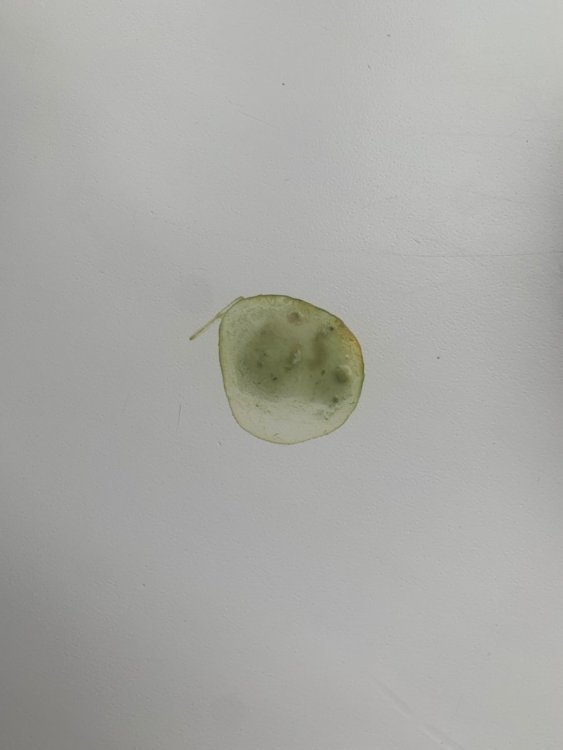

@маленький принц Сегодняшний вес 263гр. Все дозировки пересчитала на актуальный вес. Надеюсь, все верно. Лечение: -тилозин. Начат 9 сентября. Ориентируюсь давать минимум по 21 октября. Дозировка 70мг/кг. Набираю 0,6мл воды 0,1мл тилозина хорошо размешивают и выпаиваю 0,32мл полученного раствора 2 р/д. В одно время. -нистатин. Начат вместе с тилозином. Планировала давать еще неделю после окончания тилозина. Минимум по 28 октября. По 1/4 таблетки 2 раза в день. За 30-40 мин до еды. Натощак. Так как его нужно давать еще неделю и после амоксициллина, если я верно поняла, то ориентируюсь его давать до 8 ноября. -гепатовет по 0,1мл на 100гр дважды в день после еды. 0,26 сегодня буду давать. Начат так же сразу 9 сентября. Планирую давать на протяжении всего времени как даю противогрибковое. Да через 21 день остатки препарата выкидываю и покупаю новый. -Итраконазол. Дозировка 30 мг/кг/сутки. Сейчас у нас новая капсула в ней 495 пеллет. Значит с сегодняшнего дня даю по 20 пеллет два раза в день. Начат 6 октября. Не знаю какая продолжительность курса. -Юнидокс. 1/4 таблетки растворяю в 1мл воды и такого раствора выпаиваю по 0,41мл дважды в день. Храню в холодильнике сутки. Начат 6 октября. Курс 6 недель. Значит до 17 ноября. На время лечения убрать все источники кальция и витамина D. -Ацикловир. Начат в качестве профилактики, так как очень боялась заразить его оспой. 1/4 таблетки 400мг растворяю в воде и спаиваю этот раствор за два раза. Часть утром часть вечером. Начат 9 октября. Когда можно прекратить? -Амоксициллин Таблетки 250+62,5 мг Таблетку развожу в 5 мл воды спаиваю по 0,66мл дважды в день. Раствор храню в шприце с закрытым колпачком в холодильнике 5 суток. Перед отбором дозы взбалтываю. Начат 11 октября. Ориентировочная продолжительность приема 3 недели (до 1 ноября). Сама прекращать ничего не буду, все уточню. -Глюкоза. Одна часть физраствора две части глюкозы. Колю подкожно теплым. 3мл в сутки. Начата 2 октября. Не колола больше так как кормить стараюсь нормально, и его не сильно много рвало в последние дни. Но учитывая, как он стремительно тощает, может увеличить дозу? -Ципровет. По 0,1мл дважды в день подкожно в одно и то же время. Начат 15 октября вечером. Продолжительность не знаю. -Флуконазол. По 1,3мл дважды в день подкожно. Начат 15 октября вечером. Продолжительность не знаю. -отвар крапивы с 19 сентября 5 дней по 1мл 3 раза в день. Снова начат 6 октября. По 1мл 3 раза в сутки. Продолжаю давать. Или стоит прекратить? -Фоспренил. Давала два дня по 0,3мл. Наверное Фоспренил стоит подавать? По 0,26 раз в сутки. Верно? И на всякий случай, чтоб просто все в одном месте было для наглядности. Это то, что у нас было в лечении, но закончено: -глюконат кальция давала две недели с 18 сентября по 2 октября. По 0,1мл на 100гр 1 раз в сутки. -викасол с 5 октября по 0,1мл в сутки проколола 5 дней. Я вообще в ужасе, что с ним творится. Как стремительно он худеет. (Как когда-то набирал…). За 3 дня похудел на 30гр. Киль снова торчит. Его постоянно рвет. Я кормила его два дня киселем из пшеничной муки и воды, и было получше, он перестал постоянно рваться как с каши. Начала понемногу в этот кисель подмешивать каши, чтоб попитательнее было. Вот так это выглядит: Вечером покормила его этим киселем с кашей. Через час приблизительно его вырвало. Больше мучить не стала. Рано утром его снова начало рвать. И рвет его каким-то ужасом! Похоже на комок каши ярко зеленого цвета (фото не передает) со слизью! Рвет его просто бесконечно! Я с утра даже нистатин натощак задать не могла. У него рвотные позывы спазмы просто через каждые 5 минут. Наклоняется, трясется, рваться нечем, но его всего трясет колошматит… кошмар! Когда не рвет, сидит раздувает подклювье горло, прям надувает-сдувает быстро, как меха ходят, почти вибрация такая только с гораздо большей амплитудой и характерным звуком. Надеюсь, понятно, объяснила. Чуть успокоился, задала ему нистатин. Пытался вырвать, не получилось. Через полчаса покормила. Только его киселем-клейстером. Без каши. Через 20 минут снова вырвало. Последние два дня помет выглядит так: Сегодня с утра вот что выдал: Вообще с киселя у него преимущественно вода, никаких там сформированных крендельков.